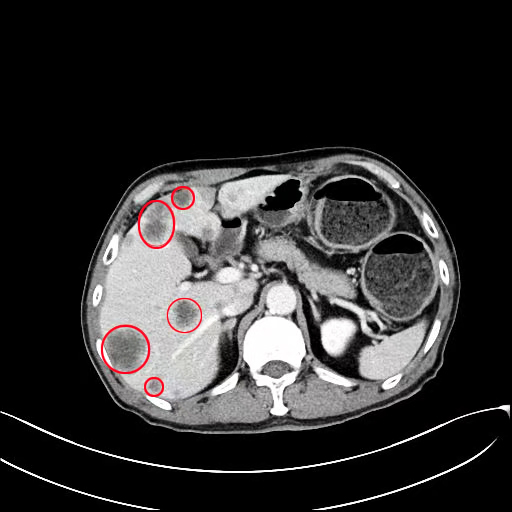

影像2020